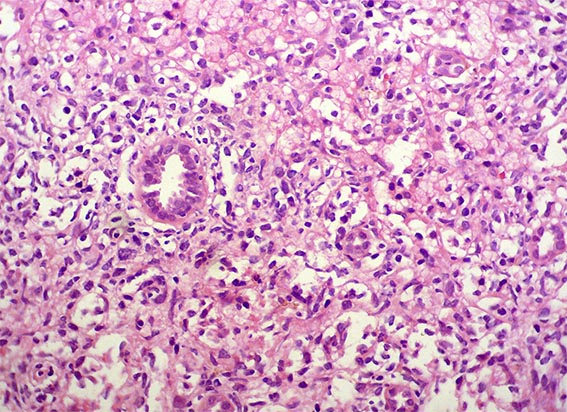

The patient is a 41-year-old woman with constitutional symptoms. Among the many studies undertaken to determine its cause, pyuria and microscopic hematuria were found in the urinary sediment, and, by ultrasonography, a ill-defined mass was evidenced on the renal upper pole of the left kidney.

A biopsy of the mass was obtained. See the images.

Figure 4. H&E, X400.